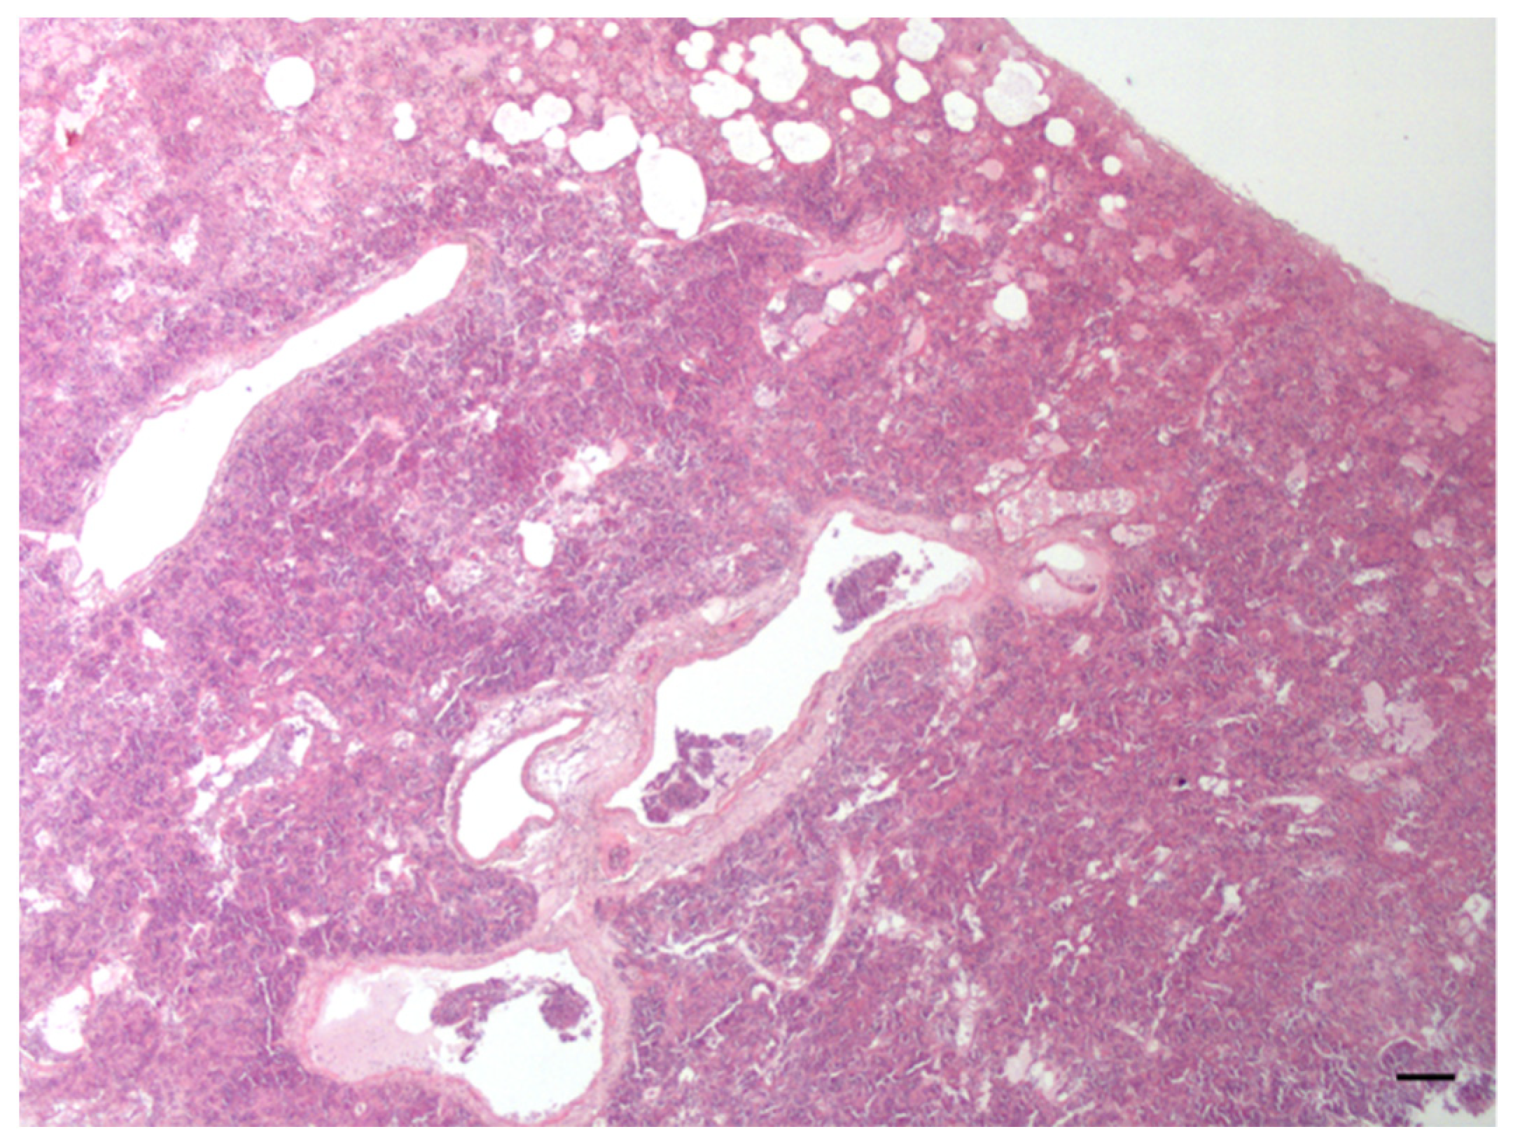

| Lymph nodes | Multicentric lymphoma | 1 |